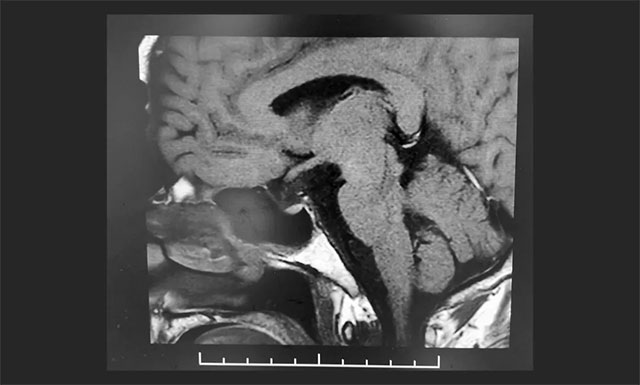

▲ 術(shù)后影像顯示腫瘤被切除

術(shù)后,根據(jù)病理檢測,患者確診為顱咽管瘤;颊咭暳^前術(shù)明顯改善,未出現(xiàn)尿崩,垂體激素?zé)o異常,精神狀態(tài)穩(wěn)定,目前正在康復(fù)中。李士其教授叮囑患者出院后仍需定時復(fù)查。